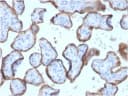

This antibody reacts with a 70 kDa membrane-bound isozyme (Regan and Nagao type) of Placental Alkaline Phosphatase (PLAP) occurring in the placenta during the 3rd trimester of gestation. It is highly specific for PLAP and shows no cross-reaction with other isozymes of alkaline phosphatase. Anti-PLAP This antibody reacts with germ cell tumors and can discriminate between these and other neoplasms. Somatic neoplasms e.g. breast, gastrointestinal, prostatic, and urinary cancers may also immunoreact with antibodies to PLAP. Anti-PLAP positivity in conjunction with anti-keratin negativity favors seminoma over carcinoma. Germ cell tumors are usually anti-keratin positive, but they regularly fail to stain with anti-EMA, whereas most carcinomas stain with anti-EMA. Anti-PLAP has been useful in the diagnosis of gestational trophoblastic disease._x000D_ _x000D_ Primary antibodies are available purified, or with a selection of fluorescent CF® Dyes and other labels. CF® Dyes offer exceptional brightness and photostability. Note: Conjugates of blue fluorescent dyes like CF®405S and CF®405M are not recommended for detecting low abundance targets, because blue dyes have lower fluorescence and can give higher non-specific background than other dye colors._x000D_ _x000D_Synonyms:

IHC, FFPE (verified) | WB (verified)Validated Applications:

IHC, FFPE, WBField of Research:

Cancer, Developmental biologyPositive Control:

HepG2 cells. Placenta or seminomaConcentration: